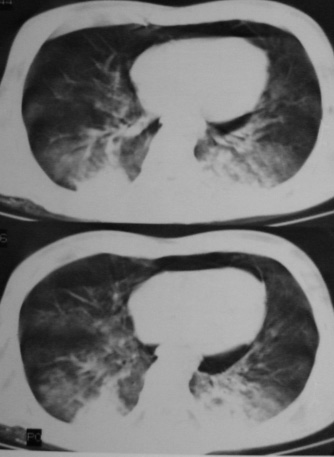

男,18岁,车祸20小时后胸ct.血氧饱和度80,呼吸45次/分.

1:双肺挫裂伤,以双下肺明显。

2:纵隔气肿。

1:两侧创伤性湿肺。